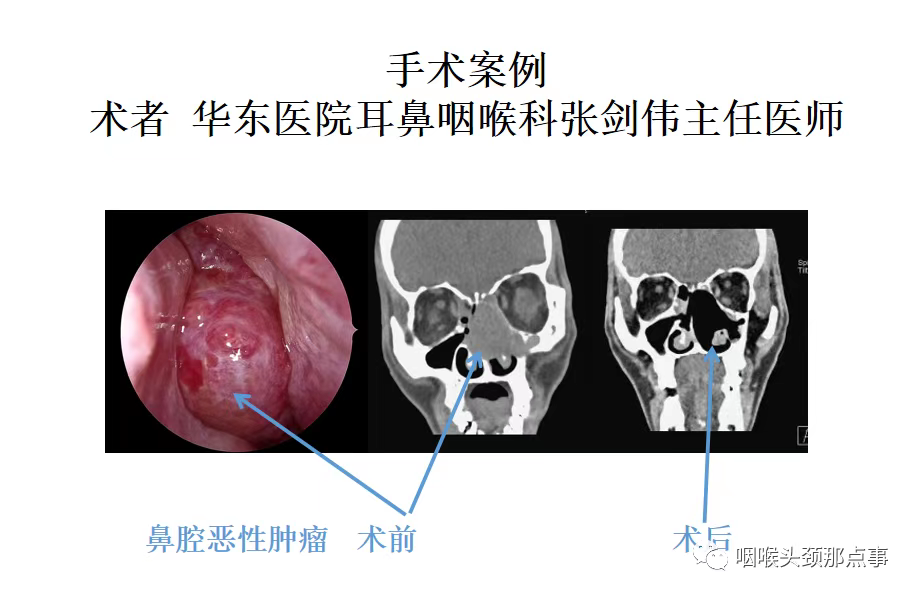

现在随着工业发展及大气污染,过敏性鼻炎患者患病率也明显增高,过敏性鼻炎常表现为鼻甲肿大,苍白水肿,患者鼻塞较明显,鼻音很重,夜间打呼憋气;肥厚性鼻炎也是重要原因之一;再有就是良性的比如鼻息肉、鼻腔乳头状瘤、骨化性纤维瘤等鼻腔堵塞;还有就是鼻腔恶性肿瘤等堵塞整个鼻腔导致的张口呼吸。

鼻腔肿瘤1

鼻腔肿瘤2